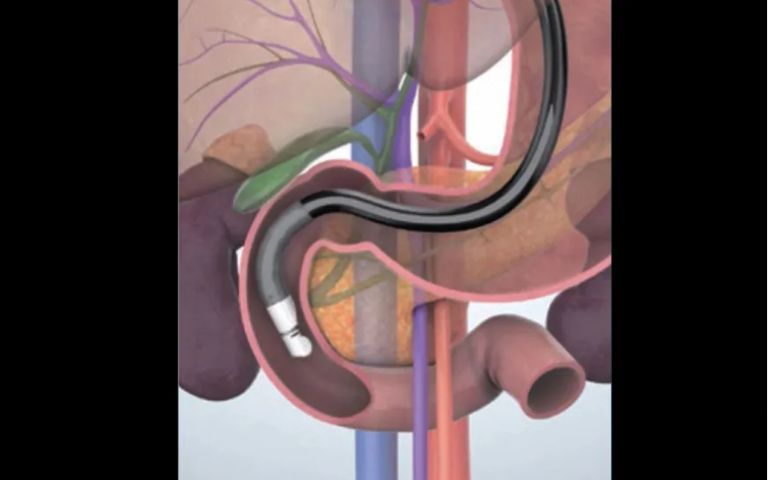

内視鏡の先端に超音波観測装置がついた特殊な内視鏡です(図1)。口から挿入して、胃や十二指腸から膵臓や胆管、胆のうを超音波装置にて観察する検査です(図2)。

▲図2:コンベックス型超音波内視鏡

通常の胃カメラとは全く違うので、食道・胃・十二指腸の観察はできません。(しかし、食道や胃・十二指腸にできた粘膜下腫瘍に関しては観察ができます。)

腹部エコーに比べると、膵臓や胆道、胆のうを詳細に観察できます。特に膵鈎部(すいこうぶ)や膵尾部といった膵臓の端っこ、胆のう管まで観察ができますが、胃の手術をされた方や、内臓脂肪の多い方は観察が不十分となることもあります。